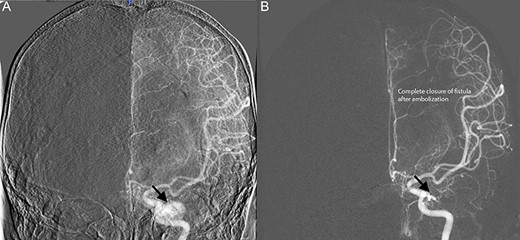

Diagnostic cerebral angiogram demonstrative of right indirect CCF. (A) Right ICA angiogram revealed indirect fistulization between the ECA branches and cavernous sinus (type D CCF) (B) with subsequent successful endovascular coil embolization.

Diagnostic cerebral angiogram (DCA) revealed bilateral indirect CCFs (type D on the right, type B on the left) with significantly higher flow on the right compared to the left (Figs 1C, 2A, 3A). A day later, through micro puncture of the right common femoral artery, coil was advanced (under real-time sonographic guidance and DCA). A microcatheter was used to access the right cavernous sinus via the left cavernous sinus through the intercavernous sinus. Right indirect CCF with arterial feeders arising from both the internal and external carotid arteries with outflow through the intercavernous sinus was confirmed. Embolization of the right cavernous sinus and intercavernous sinus was performed with 11 detachable coils and resolution of the type D carotid-cavernous flow was immediately noted (Fig. 2B); spontaneous resolution of the left type B CCF was noted (Fig. 3B) over a 24-h period of time.